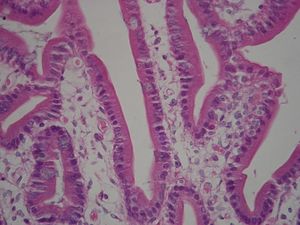

تحور الغشاء الخلوي عند السطح القمي apical surface للخلايا العمادية الطلائية Columnar Epithelium Cells الإمتصاصية ليكون ثنيات إصبعية الشكل ، تعرف بإسم "الخملات الدقيقة". وتزيد هذه الخملات الدقيقة – التي يصل طول كل منها 1-2 ميكرومتر – المساحة السطحية للغشاء ، وعادة ما تعرف بإسم "الحافة المخططة" Brush border، بينما تعرف تلك الخاصة بخلايا الأنيبيبات القريبة بالكلى Kidney proximal tubules بإسم "الحافة الفرجونية". ويحتوي لب الخملة على خييطات أكتين Actin filaments ، مرتبطة معا في حزم بروابط عرضية.